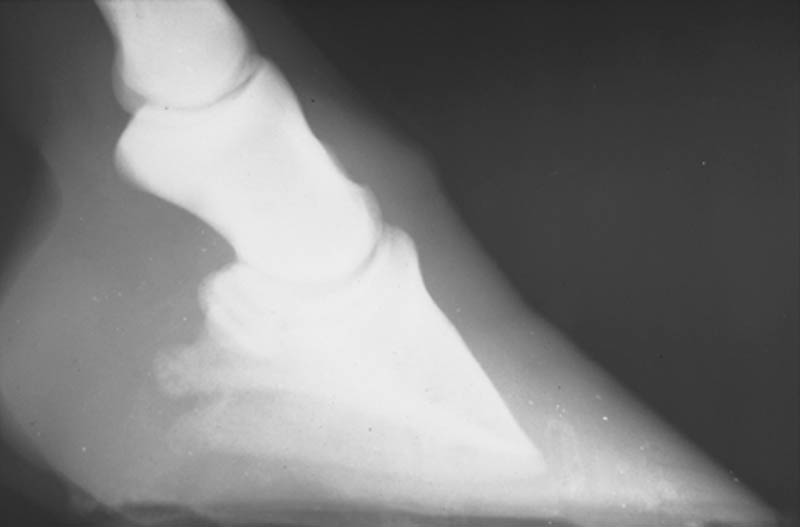

The term "Founder" is used when there is visible and measurable displacement between the hoof wall and the coffin bone. The hoof wall is no longer closely aligned nor parallel with the dorsal surface of P3. The acute and chronic stages are included, as in acute founder and chronic founder.

The horse experiences horrific pain as the laminae are torn. To understand what the horse is going through, while seated on a chair, try hooking your thumb nails on the edge of your chair then attempt to lift yourself off the chair. This tearing action does injury to the cells of the laminae tissue, and to the capillaries supplying the laminae. Subsequently, clear serum fluid and blood exude from the laminae tissue and can become painfully pressurized between the hoof wall and P3. If you have ever smashed a finger nail you know the throbbing associated with the blackened nail. In most founder cases, the hoof wall is displaced forward and upward (dorsally) at the toe until the sole comes in heavy contact with the ground. P3 is caused to be tilted downward during weight bearing, thus concentrating much of the sole load on the tip of P3. The sole corium in that area is severely overloaded and thus is painfully crushed and bruised. Within a short time the damaged sole callous can slough away, exposing the sole corium and the tip of P3. The tip of P3 becomes remodeled with an upturn. As the hoof wall is displaced vertically, the coronary area is often placed in sufficient compression to restrict to the blood supply to the area that generates new hoof wall growth. The horse experiences more pain from each of these complications. These complications can lead to permanent and irreparable damage to specific parts of the hoof.